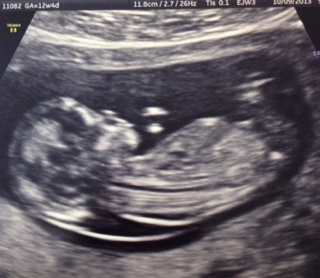

can anyone see a nub??? plz help

can anyone see a nub???

Attachment 15524